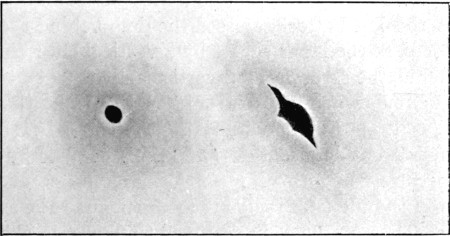

16. Entry and Exit Mauser Wounds56

17. Gutter Wound of Shoulder56

18. Oblique Gutter Exit Wound 57

19. Oval Entry, Starred Exit Wounds58

20. Circular Entry, Slit Exit Wounds59

21. Circular Entry, Starred Exit Wounds59